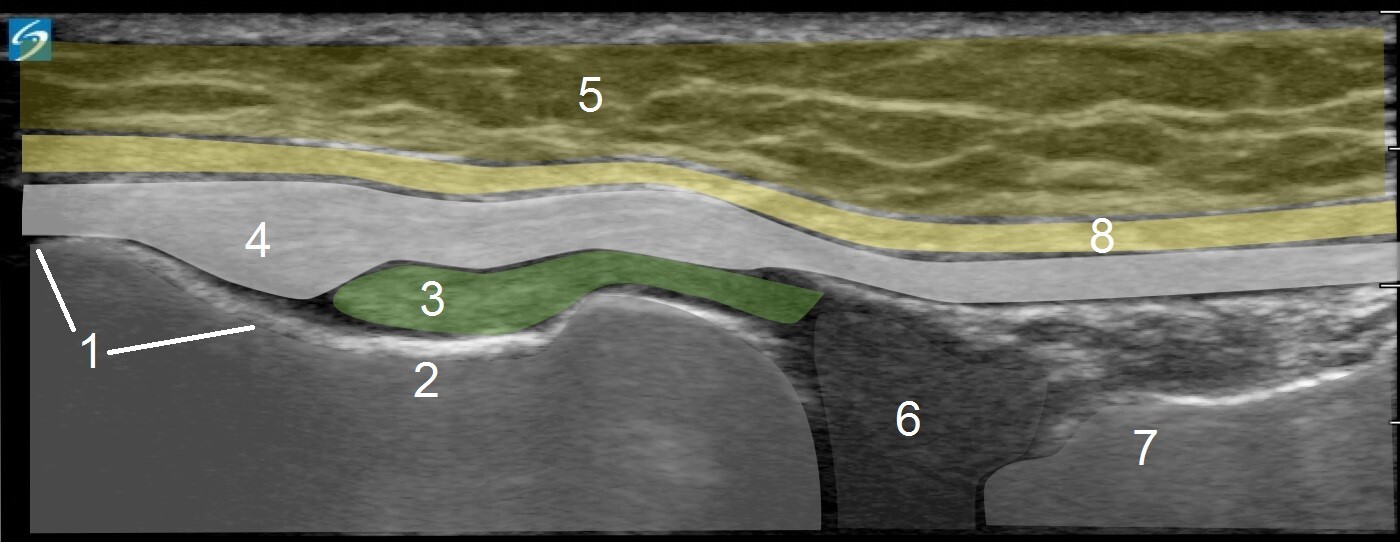

1. Lateral Epicondyle of the Femur

2. Popliteal Groove

3. Politeus

4. Proximal Lateral Collateral Ligament (LCL)

5. Subcutaneous Fat

6. Lateral Meniscus

7. Tibia

8. Fascia